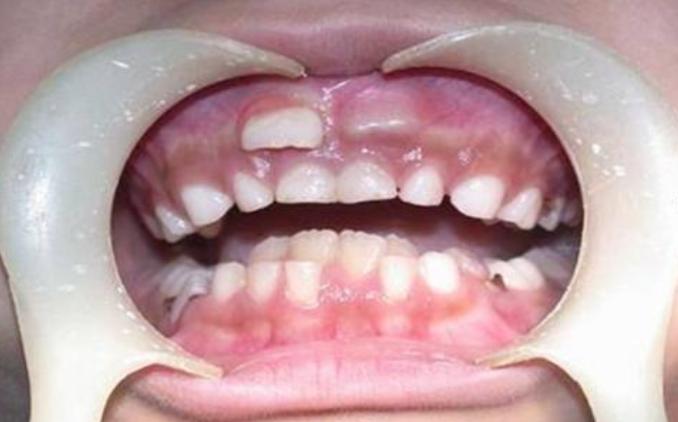

2、乳牙滞留或掉太快、磨损不够

这种情况可能会影响恒牙的发育和位置;

如出现双排牙,通过及时拔牙即可恢复到健康的状态;乳牙早失一旦发生,也可以通过检查来做间隙保持;龋齿等口腔问题更要及时处理。